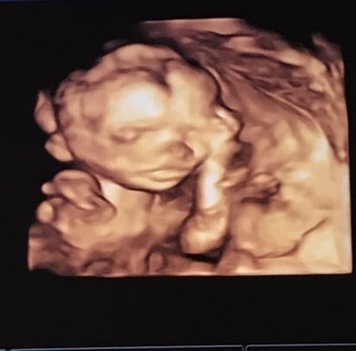

All these anatomy scans...and more boys, lol. So exciting!

We had a great anatomy scan this morning—our moms got to go with us and both cried! It was such a relief to see everything and to be reassured that little guy is developing perfectly—he weighs exactly 14 oz Thanks for all the positive vibes—still sending them out for the rest of you waiting on appointments and follow ups.

We had our anatomy scan today!! Our girl is still a girl! She looks great—heartbeat of 149, she is 11 oz and 8 inches long! Tiny little peanut!

AFM I had my anatomy scan this week as well. Confirmed that we are having boy/girl twins and they are looking great!!! Fortunately, the tech talked me through everything as she was doing it. She couldn't tell me numbers or what thinhs meant, but pointed everything out as she was taking pictures. Then, the doctor looked through everything, came in and took some extra pictures of her own "cause it's fun" and told us that our babies are doing great and everything looked perfect! I probably got the extra time and interaction cause we were at MFM with the twins, but it was great to know everything right then!